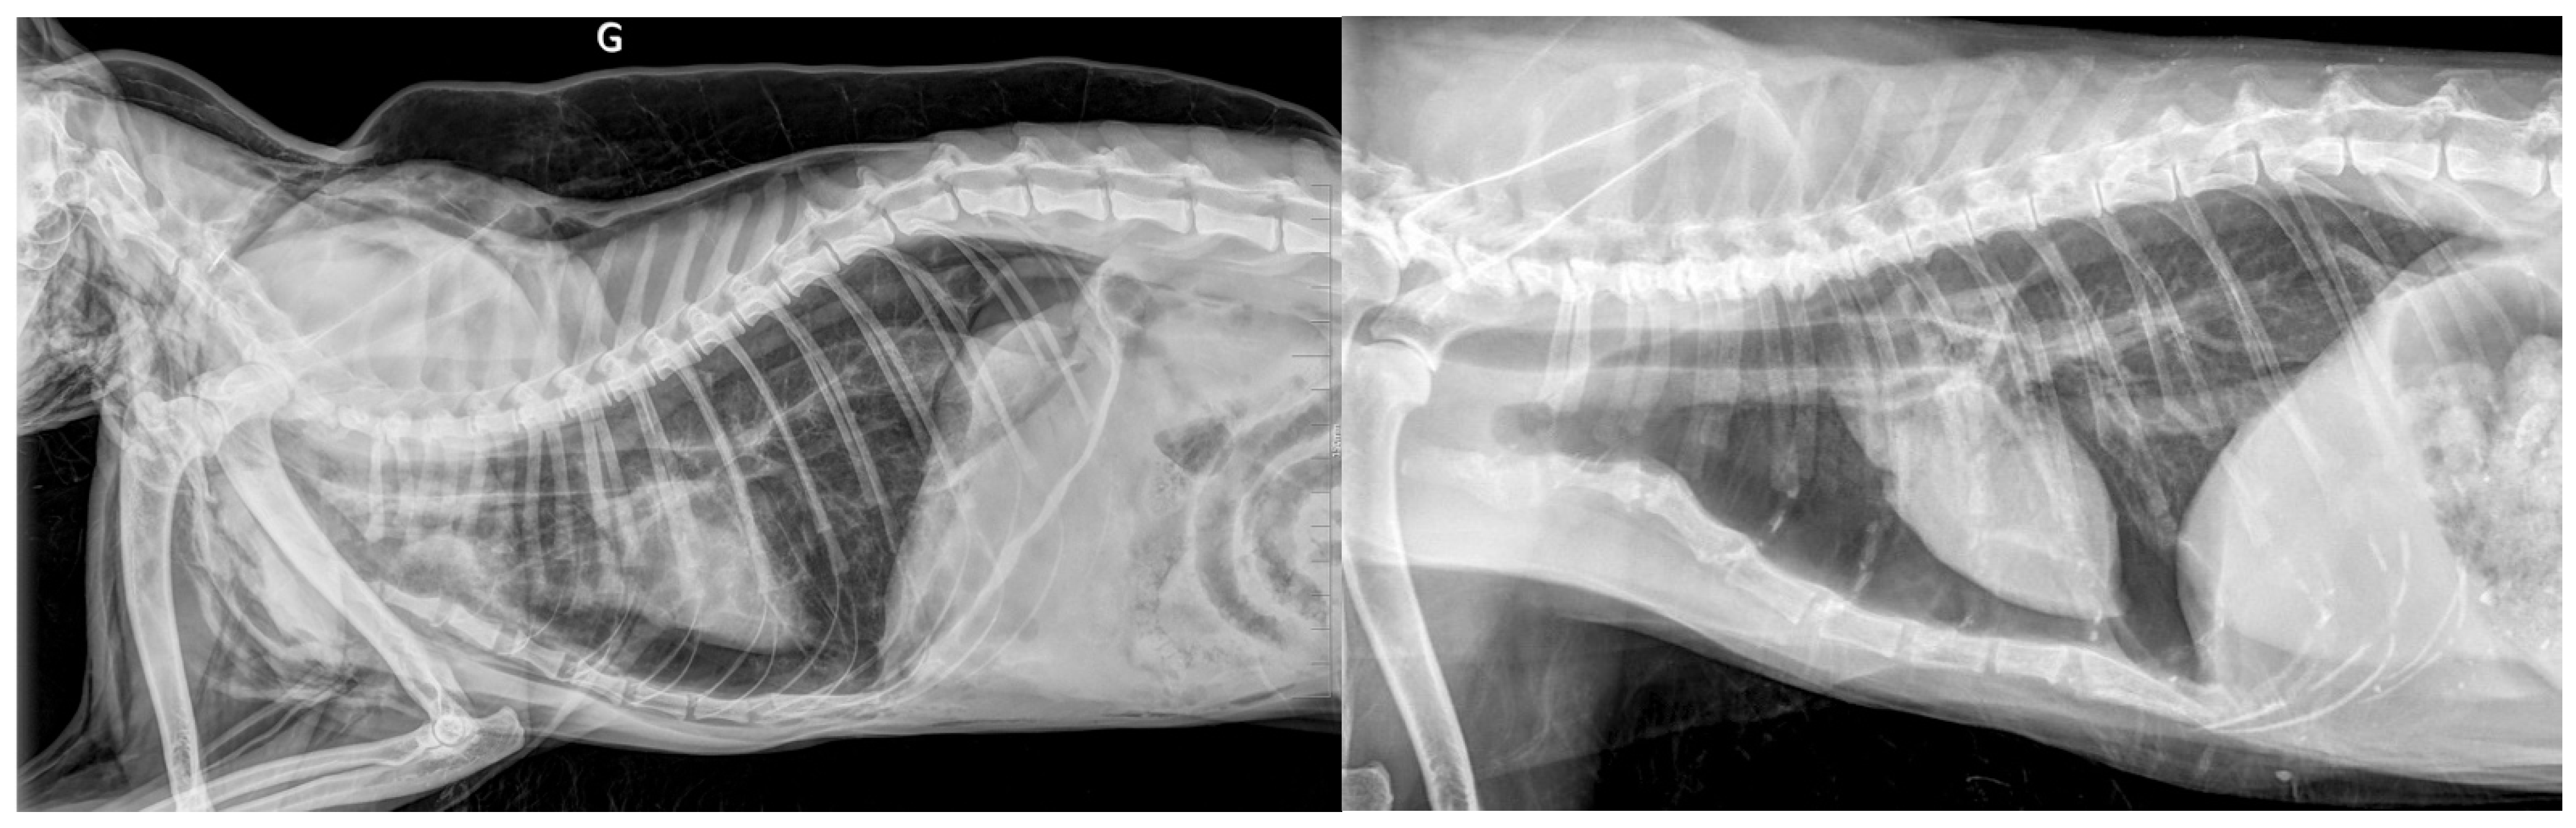

3.4. Results for Cats in Group T—Traumatic Origin